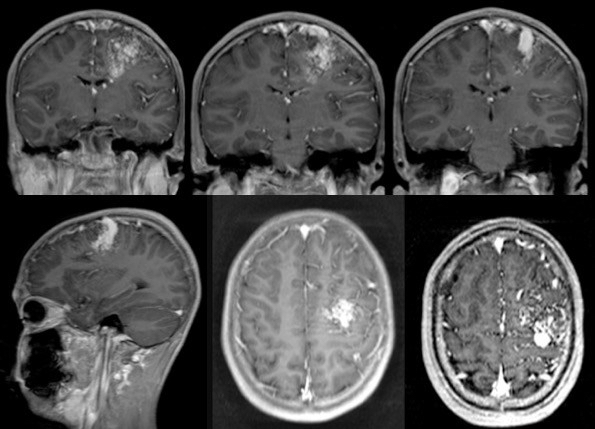

certains MAV, comme celle présentée ci-contre, ne peuvent pas être traitées sans infliger des séquelles majeures et doivent être respectées. on doit donc se contenter d’un traitement symptomatique.